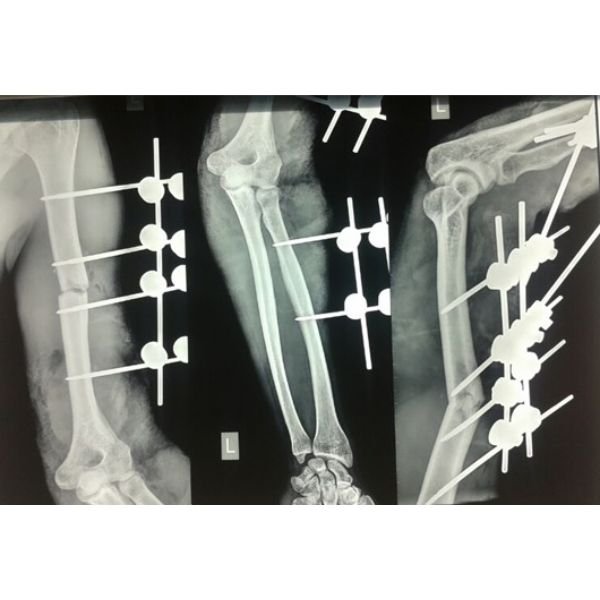

Complex Leg Injury

Femur Fracture Repair